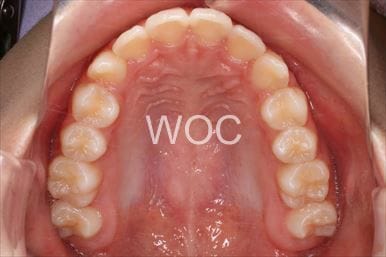

出っ歯マウスピース型(カスタムメイド)矯正装置(インビザライン)

マウスピース型(カスタムメイド)矯正装置(インビザライン)を希望。非抜歯治療の選択。装置装着時間を守り定期的に通院したため、予定より短い期間で治療を終わることができました。

- 年齢:23歳女性

- 主訴:出っ歯、口が閉じにくい

- 基本矯正料金:895,000円

- 治療期間:1年10ヶ月

- 非抜歯